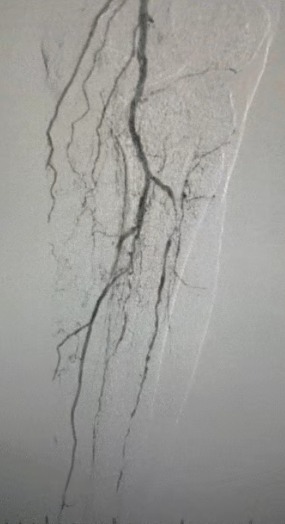

Los hallazgos clínicos

· Examen físico: Pulsos femorales débiles; ausencia de pulsos poplíteo y dorsalis pedis; ulceración en el primer dedo del pie izquierdo; necrosis en el primer y segundo dedo del pie derecho

· Imagen preoperatoria: estenosis calcificada difusa y grave en arterias bilaterales de las extremidades inferiores

Resultado quirúrgico

Después del procedimiento, la estenosis arterial mejoró significativamente, el flujo sanguíneo aumentó y la temperatura de la piel aumentó. No hubo complicaciones postoperatorias. Tanto el paciente como el equipo quirúrgico estaban muy satisfechos con los resultados.